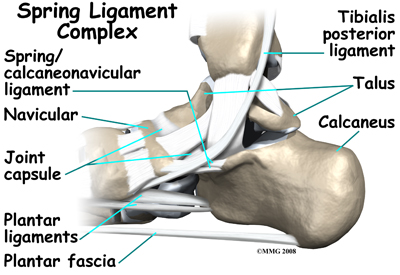

Many small ligaments hold the bones of the foot together. Most of these ligaments form part of the joint capsule around each of the joints of the foot. A joint capsule is a watertight sac that forms around all of the joints of the foot. The capsule is made up of the ligaments around the joint and the soft tissues between the ligaments that fill in the gaps and form the sac.

The plantar fascia is a thick band of ligamentous tissue on the bottom of the foot that extends from the heel to the toes. When you pull your toes back with one hand, you will be able to feel this band with your fingers of the other hand. This fascia is also critical in supporting the long arch of the foot and in creating the rigid foot structure mentioned above.

The spring ligament complex, which supports the talonavicular joint, is often involved in the flatfoot condition. The spring ligament complex works with the posterior tibial tendon and the plantar fascia to support and stabilize the longitudinal arch of the foot. Laxity of the ligaments that support this arch can result in deformity of the foot and/or ankle resulting in pes planus.

Foot Anatomy Ligaments & Tendons